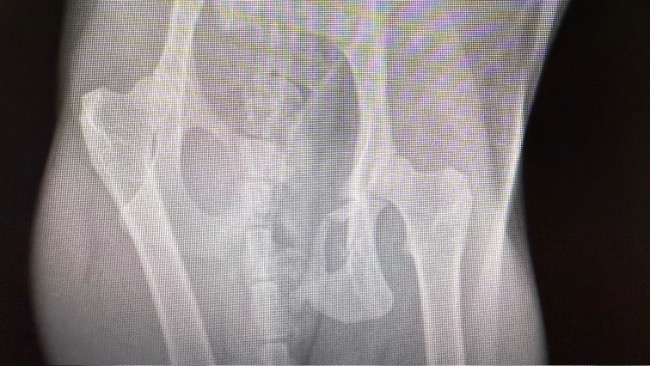

Dostaliśmy zgłoszenie z gminy Liszki o kotce potrąconej przez samochód. Gmina odmówiła pomocy, nie mają pieniędzy na takie zabiegi, zwierzęta często poddawane są eutanazji. My nie mogliśmy odmówić. Sytuacja była pilna. Okazało się, że kotka na złamaną miednicę. Przed zabiegiem musiała mieć przetoczoną krew, parametry czerwonokrwinkowe nie pozwalały na znieczulenie. Bardzo dziękujemy dziewczynom z fundacji Stawiamy na łapy, za natychmiastową pomoc, jeszcze tego samego dnia udało się znaleźć dawcę krwi i wzmocnić kotkę przed zabiegiem. Pimpa miała też wielkie szczęście, bo udało się znaleźć termin na CITO u świetnego ortopedy dr Rafała Korty z lecznicy Arwet, który złożył jej miednicę. Na chwilę obecną kotka jest bardzo słaba, ale dzielnie walczy. Niestety nie sika samodzielnie, jest cewnikowana. Nie chce też jeść, jest dokarmiana przez sondę. Za to parametry czerwonokrwinkowe poprawiają się. Czeka ją długa rekonwalescencja, przed nami jeszcze kastracja, oraz zabieg stomatologiczny, ale to dopiero po ustabilizowaniu stanu zdrowia. Dziękujemy też zespołowi Luxvet24 w Krakowie, za świetną opiekę zarówno przed, jak i po zabiegu. Bardzo prosimy o wsparcie, to dopiero początek walki o jej życie i zdrowie. Każda złotówka jest na wagę złota !